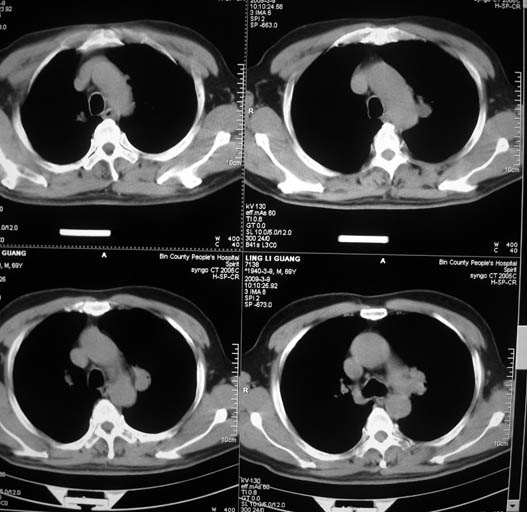

以下是引用随光逐影在2009-3-9 21:36:00的发言:[br]1)两肺上叶尖段结节状病灶,性质待定(不排除肿瘤可能);建议追踪复查。2)右肺中叶内侧段炎症。